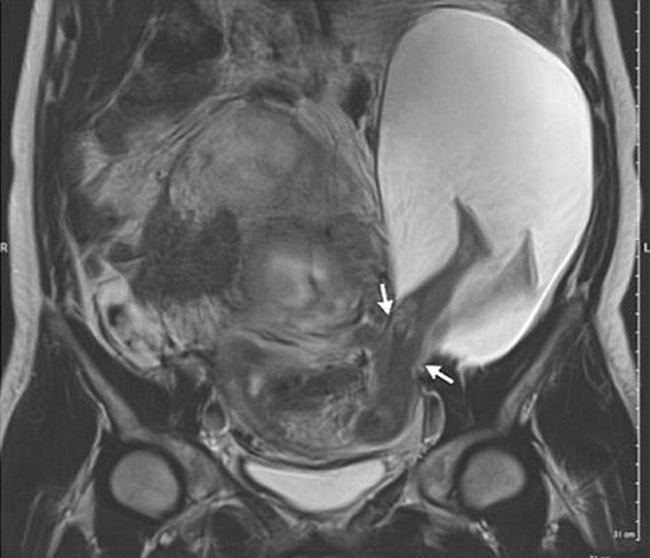

Hình chụp siêu âm cho thấy em bé đã đạp rách tử cung khi vẫn nằm trong bụng mẹ.

Trường hợp mang thai kỳ lạ này đã được bác sĩ Pierre Emmanuel Bouet, thuộc Bệnh viện Đại học Angers phát hiện ra sau khi nhìn thấy hình siêu âm của một sản phụ 33 tuổi. Theo bác sĩ, đây là 1 trong 26 ca mang thai cực hiếm hoi trong lịch sử y học thế giới.

Vết rách có chiều dài 2,5cm. Một phần túi nước ối cũng theo đó mà lòi ra ngoài. Trước tình trạng này, bác sĩ đã cảnh báo khả năng sinh non cũng như thoát vị tử cung, nhau cài răng lược, thậm chí phải cắt bỏ tử cung ở mẹ.